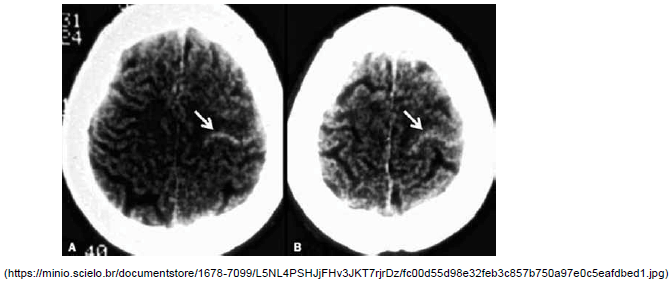

A imagem identificada na tomografia de crânio sem contraste a seguir, denominada sinal do cordão, pode ser encontrada em qual doença?

Provas